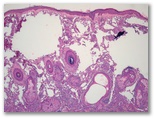

Nodulos equimóticos en región preauricular y retroauricular